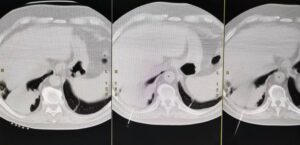

Medicii radiologi și chirurgii toracici ai Spitalului Clinic Județean de Urgență (SCJU) Sibiu au reușit o premieră, efectuând prima biopsie pulmonară CT ghidată. Procedura a fost realizată în cadrul Radiologie și Imagistică Medicală.

Acest tip de biopsie este o intervenție minim invazivă care permite recoltarea, cu ajutorul unui ac de biopsie, a unui fragment de țesut dintr-o formațiune suspectă imagistic, sub ghidaj CT. Metoda este utilă pacienților cu formațiuni pulmonare neoplazice din Spitalul Clinic Județean de Urgență, pacienților din celelalte spitale din județul Sibiu, dar și din județele limitrofe.